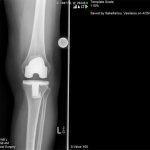

Ο ορθοπεδικός – χειρούργος Βασίλειος Σακελλαρίου στην Αθήνα αντιμετωπίζει επιτυχώς κάθε είδους κακώσεις γόνατος και ισχίου. Παρακάτω παρουσιάζονται πολλές περιπτώσεις κακώσεων που αντιμετωπίστηκαν επιτυχώς από τον χειρούργο – ορθοπεδικό. Δείτε τις αναλυτικά: